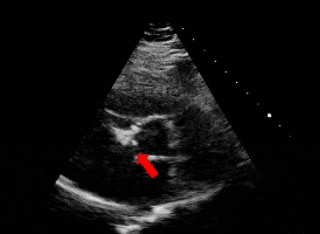

释放前瓣上造影,分流明显减少(左);牵拉试验,确认封堵器稳定(右)

释放后评估

封堵器形态良好,基本无残余分流